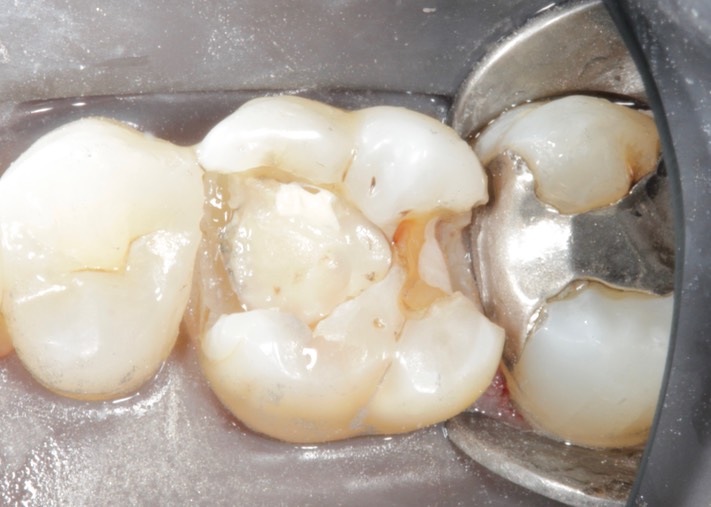

Gary Umeda #3 caries removal